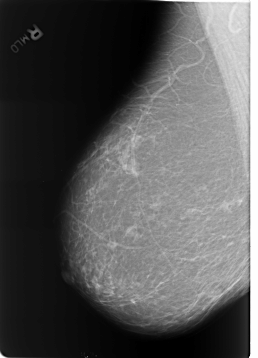

B_3253_1.RIGHT_MLO

LEFT_MLO LINES 5632 PIXELS_PER_LINE 4160 BITS_PER_PIXEL 12 RESOLUTION 50 OVERLAY

FILE: B_3253_1.LEFT_MLO.OVERLAY

TOTAL_ABNORMALITIES 3

ABNORMALITY 1

LESION_TYPE CALCIFICATION TYPE LUCENT_CENTER DISTRIBUTION N/A

ASSESSMENT 2

SUBTLETY 5

PATHOLOGY BENIGN_WITHOUT_CALLBACK

ABNORMALITY 2

ABNORMALITY 3